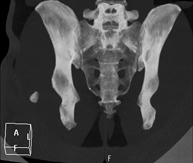

Exploració radiològica que mitjançant un sistema de raigs X i detectors que giren al voltant del pacient i que reconstrueixen les imatges per ordinador (TC Multidetector), permet l'estudi detallat dels ossos, els músculs i les articulacions de la mà i el canell. - TC de la pelvis òssia

Exploració radiològica que mitjançant un sistema de raigs X i detectors que giren al voltant del pacient i que reconstrueixen les imatges per ordinador (TC Multidetector), permet l'estudi detallat dels ossos, els músculs i les articulacions de la pelvis. - TC de malucs

Exploració radiològica que mitjançant un sistema de raigs X i detectors que giren al voltant del pacient i que reconstrueixen les imatges per ordinador (TC Multidetector), permet l'estudi detallat dels ossos, els músculs i les articulacions del maluc. - TC de sacroilíaques